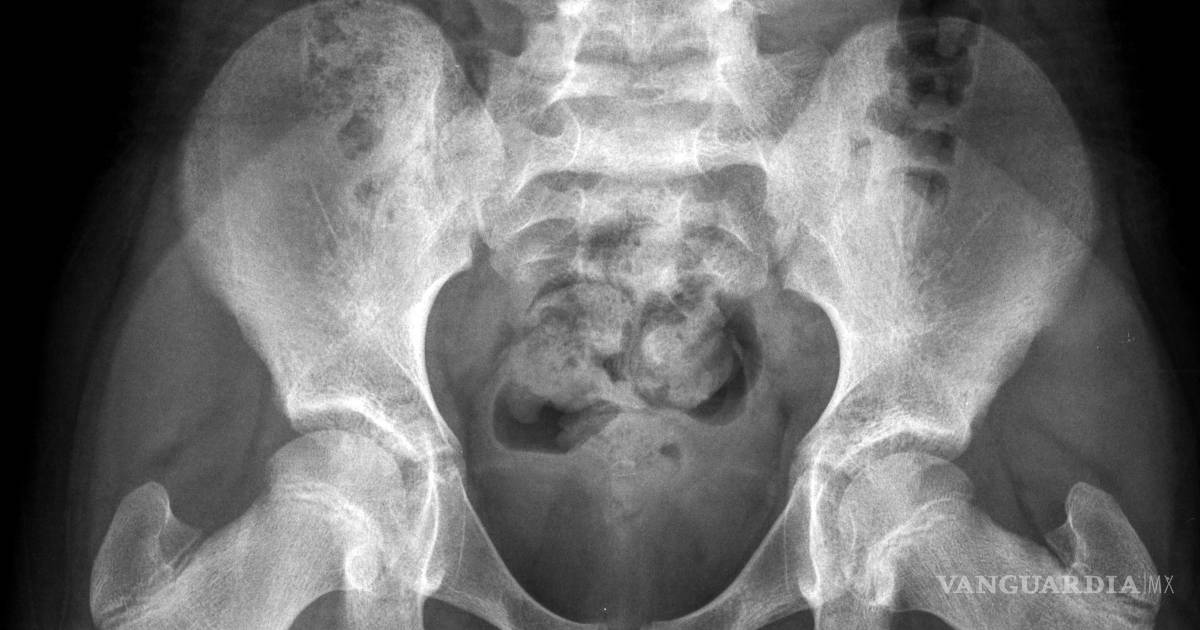

El principal problema es que la pelvis de las niñas es demasiado estrecha como para que pueda pasar incluso un feto pequeño, señaló Ashok Dyalchand, un médico que ha trabajado con adolescentes embarazadas en comunidades de bajos ingresos en la India durante más de 40 años.

“La labor de parto que experimentan es prolongada y obstruida, el feto aplasta la vejiga y la uretra” y a veces provoca la enfermedad pélvica inflamatoria y la ruptura de los tejidos que hay entre la vagina y la vejiga y el recto, señaló Dyalchand, quien dirige el Instituto de Gestión Sanitaria Pachod, que es una organización de salud pública que atiende a las comunidades marginadas en la zona central de la India.

“Las chicas pasan por un trabajo de parto de tres, cuatro, cinco días y después de ese tiempo, el bebé casi siempre está muerto. Y el bebé sale cuando se hunde la cabeza”, explicó Syed, quien es uno de los especialistas más prominentes de Asia del Sur en la reparación de la fístula obstétrica, un resultado habitual del parto obstruido en las niñas embarazadas.

En casi todos estos casos, la niña desarrolla una fístula vesicovaginal, que es un agujero entre la pared de la vejiga y la vagina. En una cuarta parte de los casos, el trabajo de parto prolongado también origina una fístula del recto, por lo que la chica deja salir orina y excremento de manera constante.